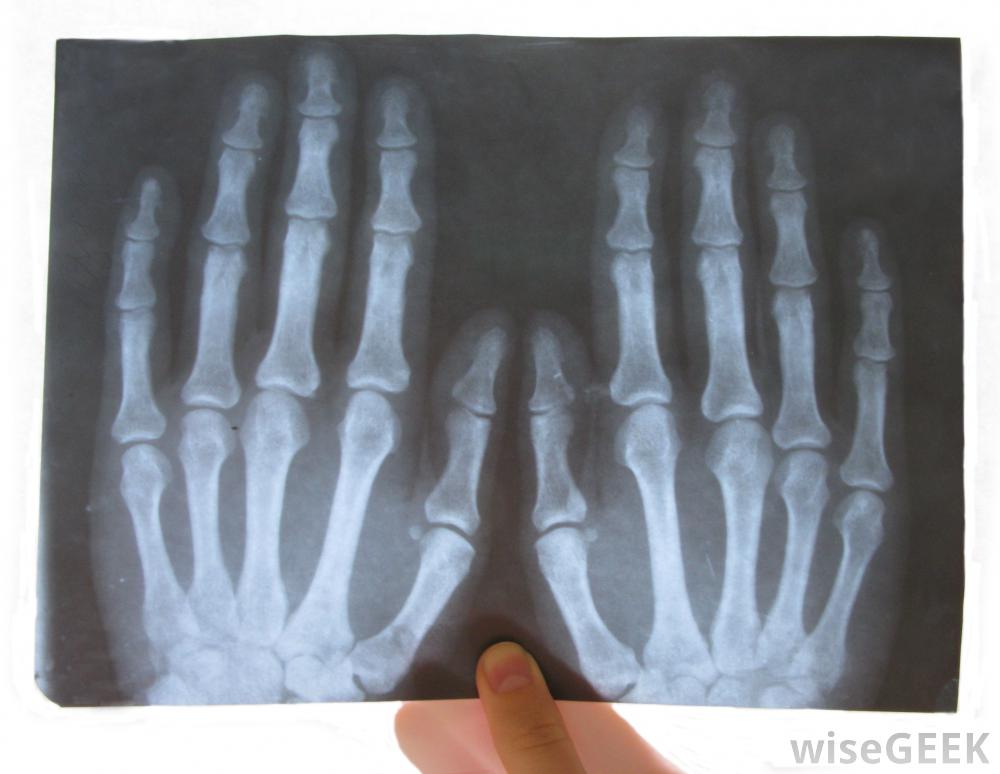

腕掌侧凸是由于外伤、劳损或先天性疾病在手腕顶部形成的骨质肿块。在某些患者中,它可能是良性的,除非它生长或开始引起问题,否则不需要任何行动。其他患者需要治疗来解决疼痛、酸痛,在许多情况下,如果保守治疗不能有效的话,"/要密切注意受累的手腕,尽早发现复发的迹象。有些患者出生时有腕掌骨肥大,而有些患者在中年时出现这种症状。肿胀可能出现在手腕上,掌骨关节的地方。这应该摸起来很硬,而且可能因为炎症而发热。这种情况有时会与神经节囊肿混淆,因此必须进行彻底的评估,以确定手腕上部肿胀的原因当然,患者的诊断是正确的。神经节囊肿可能会在腕掌骨旁形成创伤史可以作为一个潜在的指标,重复性压力也可以关节周围的慢性炎症可能会导致骨刺的形成,随着时间的推移,腕掌侧隆凸的基本治疗方法可以包括消炎药来减轻肿胀和阻止生长。夹板和适当的支撑也可以帮助,尤其是当重复性劳损是罪魁祸首时,那些继续经历疼痛和僵硬的患者可以讨论更具攻击性的选择。在大多数情况下,医生只会建议积极治疗在其他方法无法缓解不适和行动不便后。在手术中,护理人员可以去除骨刺并抚平周围的骨头,以阻止这种情况的复发在腕掌骨旁形成一个神经节囊肿,在这种情况下,它也需要切除。在愈合过程中,病人可以戴上支撑关节和促进康复的支架。一旦医生认为安全,就可以移除这些支架。定期检查以确定骨刺是否正在恢复生长,这是可以的在某些情况下,这是一个值得关注的问题。在腕掌侧弯的愈合过程中,患者可能会佩戴牙套来支撑腕部区域并促进康复有腕掌侧弯病史的人可能需要密切关注受影响的腕关节,尽早发现复发的迹象。如果医生不能清除所有的生长,或者没有充分剃掉周围的骨头,手术可能会失败。药物也可能无法抑制骨刺的复发,尤其是当患者停止服用或不定期服用时,可以通过影像学研究来追踪随时间推移的腕掌侧肌群,以便医生确定可能引起关注的变化。神经节囊肿的横切面,可发生在腕掌骨旁重复性压力可能导致腕掌侧肌群。